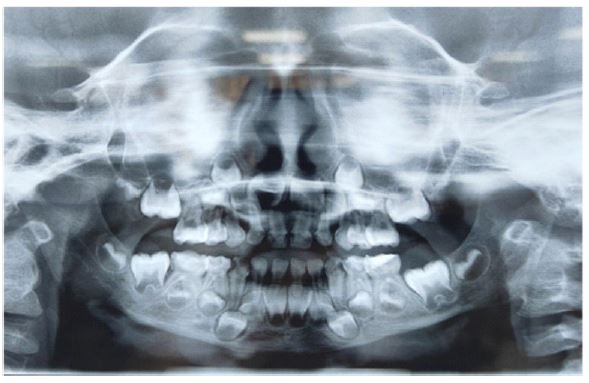

The provisional diagnosis was a combined fracture of the left para symphysis associated with a right mandibular body, and Cone beam computed tomography (CBCT) was suggested to confirm it. The Orthopantogram (OPG) and Cone beam computed tomography (CBCT) preoperatively confirmed left para symphysis fracture with a step at the inferior border of the mandible. An associated minimally displaced fracture was present on the right mandibular body region (Figures 2,3). Routine hematological investigations were advised, and emergency treatment was started. Meanwhile, antibiotics and analgesics were prescribed, along with a dose of tetanus toxoid injection. Intravenous fluids were also prescribed since the child was unable to take food orally.

Figure 2: Preoperative orthopantomogram (OPG) reveals right mandibular body and left mandibular para symphysis fracture.